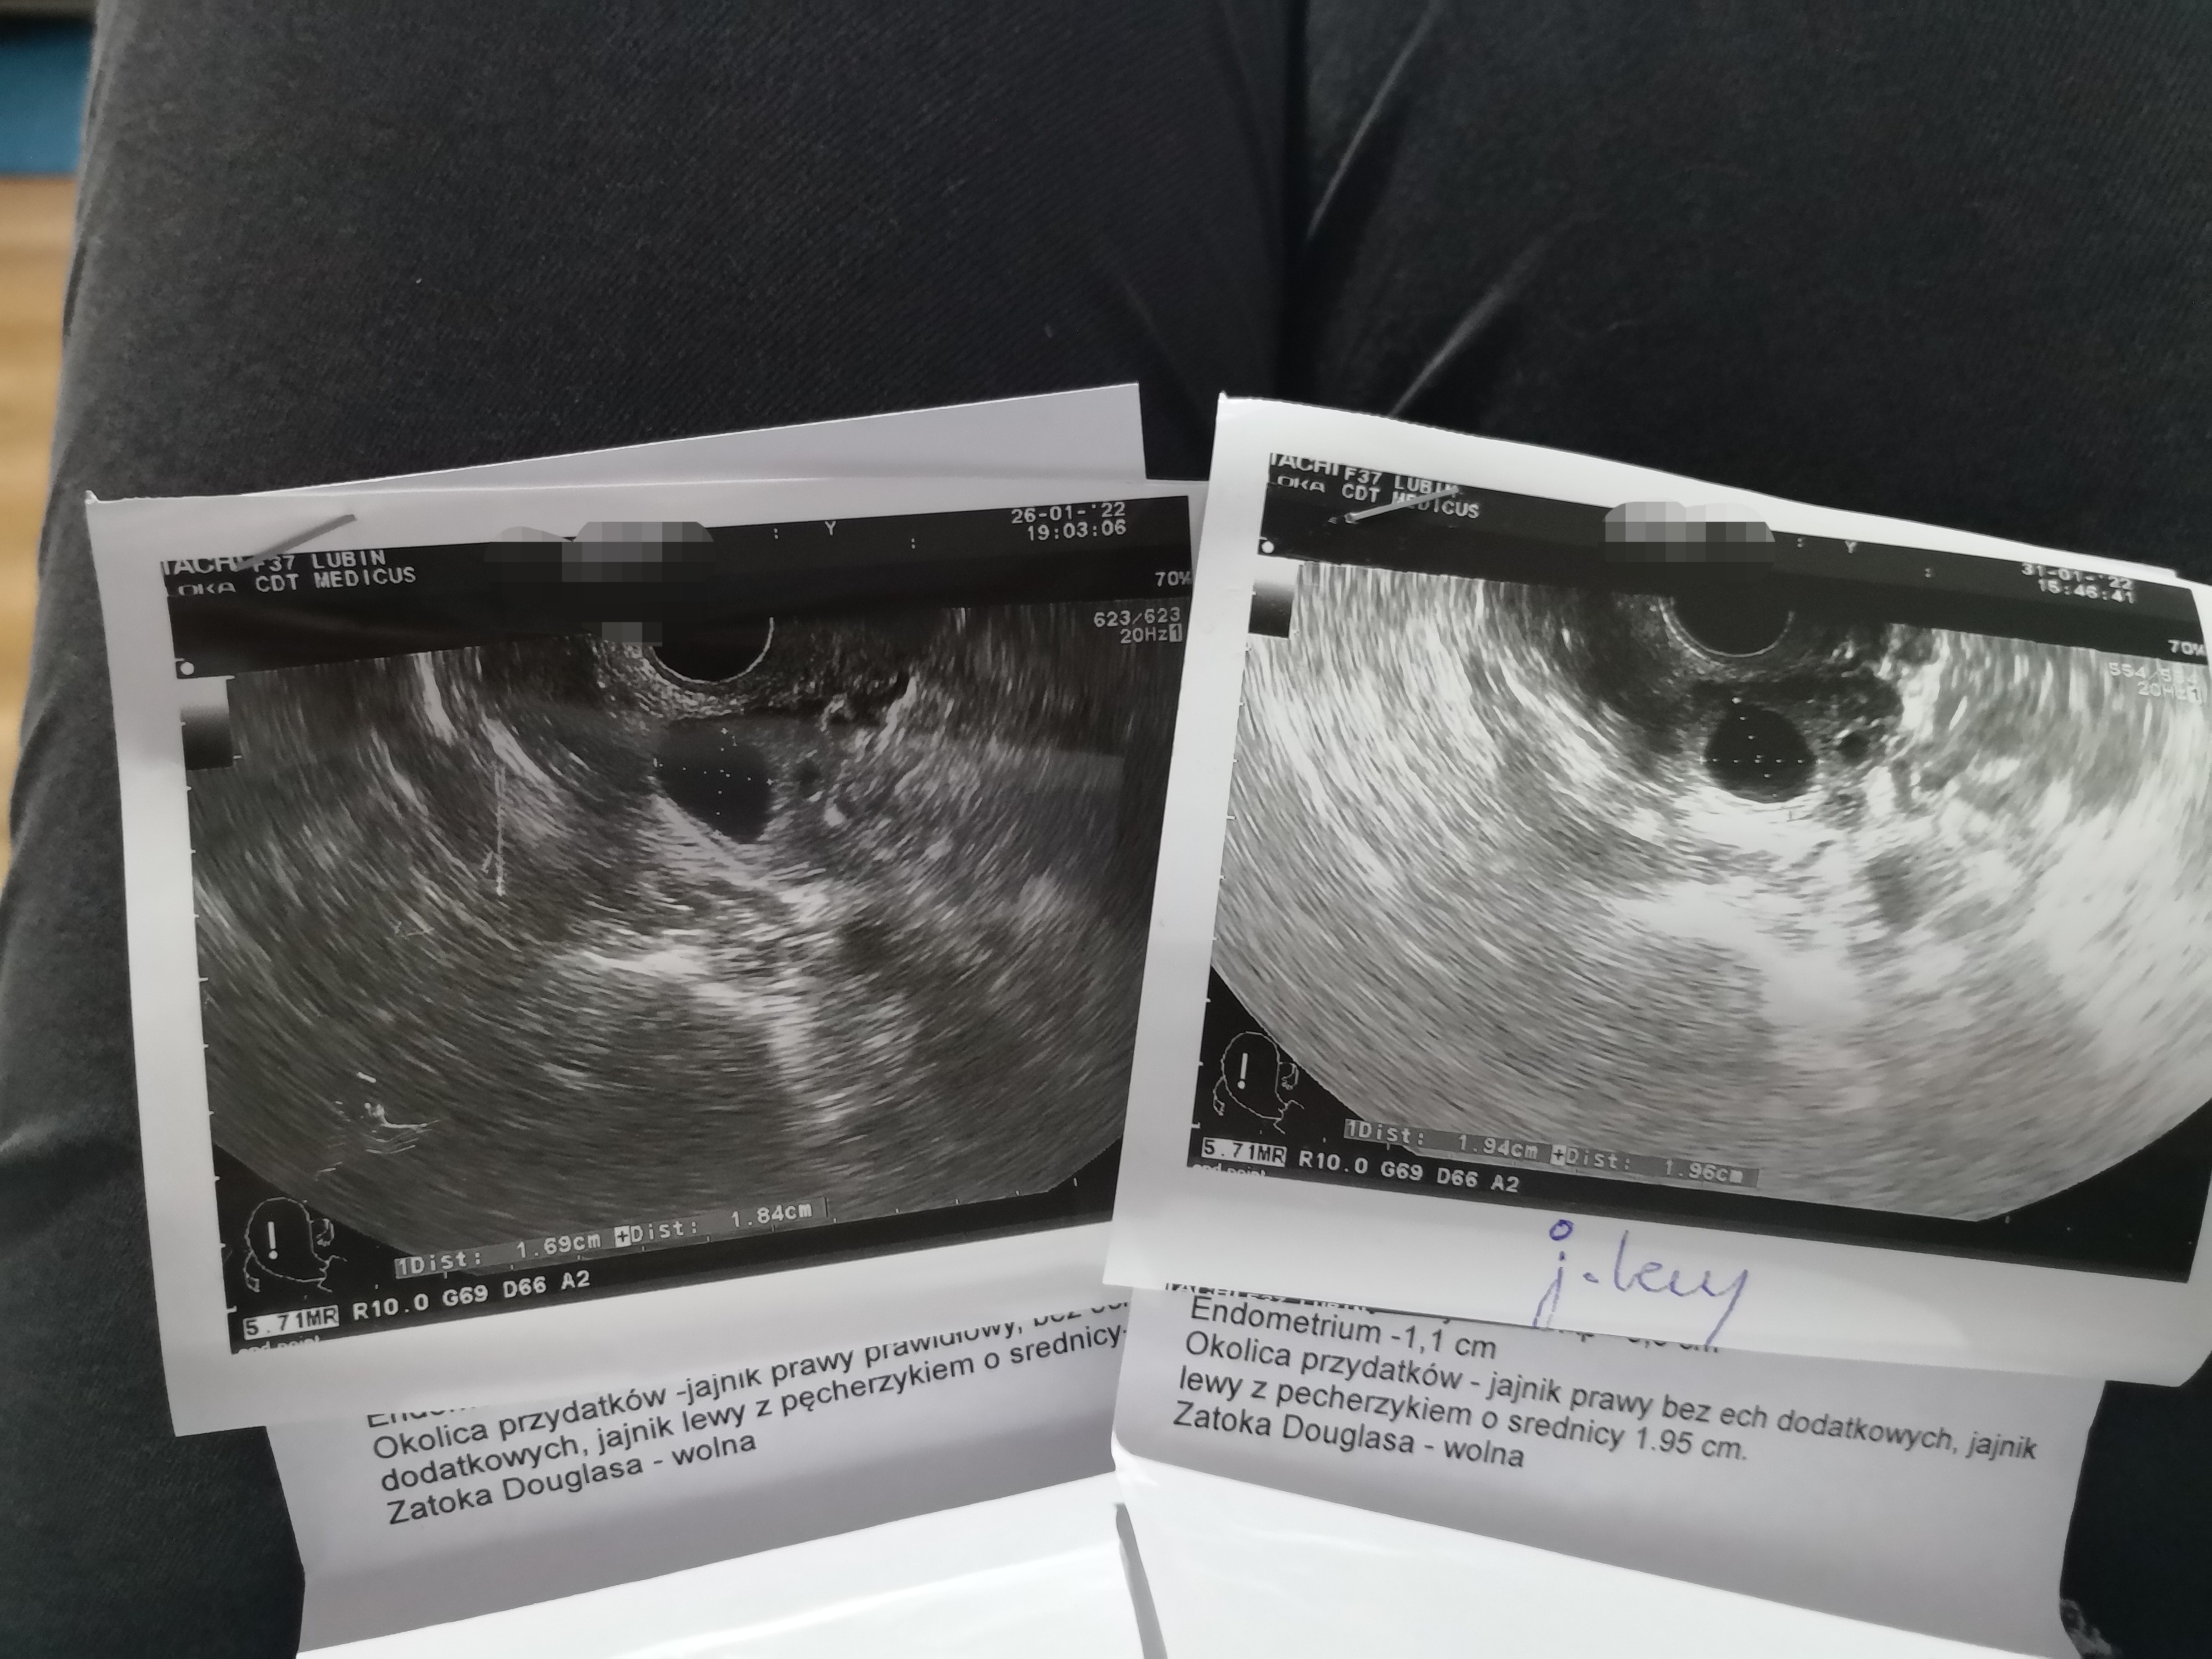

Ja Wam jeszcze wrzucę zdjęcia usg porównywawcze 😂 tam gdzie jest podpis j.lewy długopisem to zdjęcie z dziś czyli 18dc, natomiast drugie to zdjęcie ze środy 13dc - może Wy coś więcej zobaczycie 🙊🙉🙈

wygląda jakby bardzo powoli sobie rósł... chyba, że centralnie pod pierwszym był drugi, nie wiem jak dokładnie było robione usg? Tylko gdyby z jednego była już owulacja to zacząłby być wydzielany progesteron od czego bielałoby endometrium na usg... mówiła lekarka coś w tym temacie?

Ginekologiem nie jestem ale wygląda jak pęcherzyk przed owulacja po prostu ☺️ a na torbiel za małe... Mi pęka 21-26 mm dopiero... Torbiel mam ja i ma ponad 3 cm 😎 więc widzisz do tego jeszcze Ci daleko ☺️

mówiła tylko, że piękne endometrium i ładnie przygotowane na przyjęcie zarodka. Zastanawia mnie w takim razie skok temperatury od piątku (15dc) utrzymujący się do dnia dzisiejszego, czyli 4 dni - jak to nie od proga to od czego? Czuję się tak samo jak zawsze po owu, właśnie jakby progesterom działał 😂 Nic nie kumam z tego 🙄